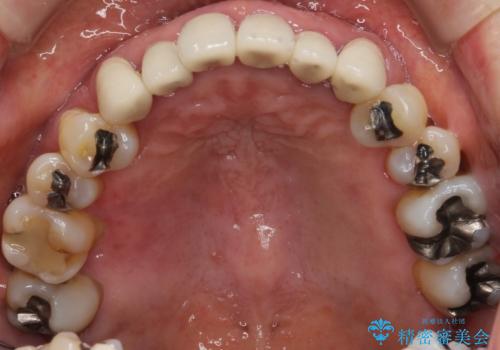

歯周病 インプラントによる咬合機能回復

- 歯が全体的にグラグラし、しっかりと物が噛めなくなり歯周病治療を希望され来院されました。

残すことのできる歯、残すことのできない歯を初期治療を進めながら見極め、最終的に臼歯部はインプラント、上顎前歯は入れ歯による補綴計画となりました。